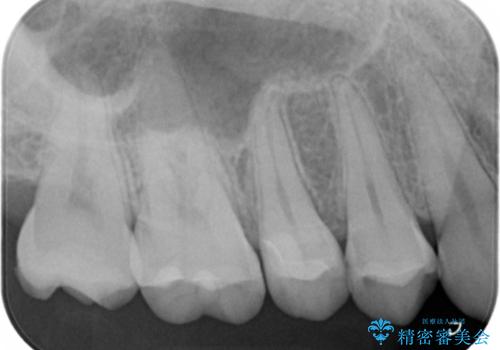

検査の結果、症状はないものの右上の奥歯に虫歯が見つかりました。

局所的に深い虫歯が確認されましたが、神経は温存することができました。

歯と歯の間から広がる虫歯は目視では確認しにくいため、定期的にチェックし悪化を予防することが大事です。